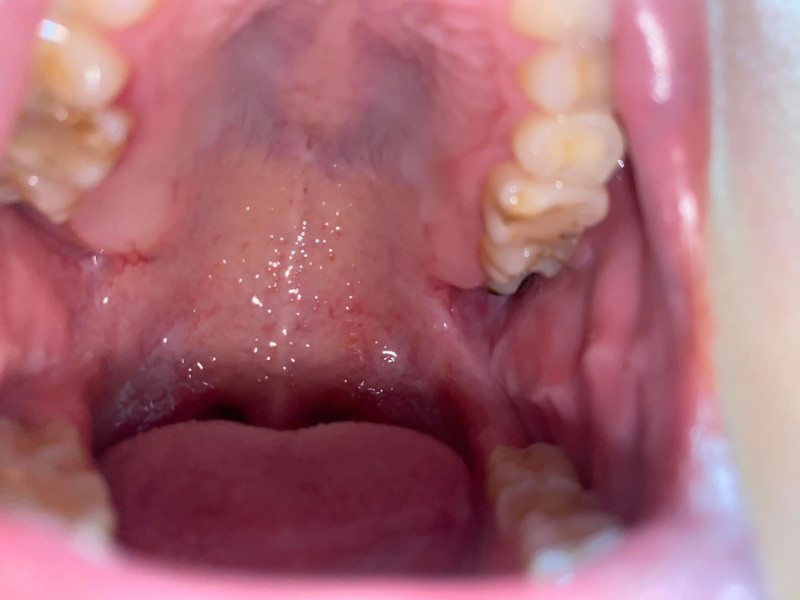

Xin chào bạn, bạn vui lòng cung cấp hình ảnh để được bác sĩ tư vấn cụ thể hơn nhé. Trân trong